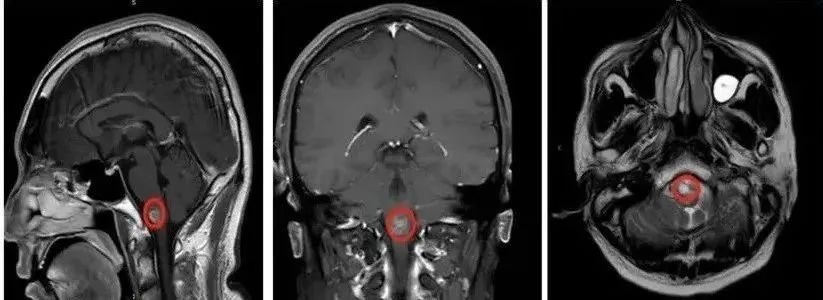

术前影像

检查结果提示脑干(桥脑下部及延髓)占位性病变,考虑脑海绵状血管瘤伴出血。

间隔一月第二次出血: 症状加重,出现显著头晕、乏力、视力模糊、行走倾倒。影像学提示本次脑干出血量更大(>5ml),波及脑桥双侧基底及被盖部,病情危重。面临严重并发症风险,如意识障碍、肺部感染、消化道出血、深静脉血栓等。